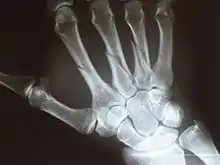

Fracture

The neck of a metacarpal is a common location for a boxer's fracture, but all parts of the metacarpal bone (including head, body and base) are susceptible to fracture. During their lifetime, 2.5% of individuals will experience at least one metacarpal fracture. Bennett's fracture (base of the thumb) is the most common.[4] Several types of treatment exist ranging from non-operative techniques, with or without immobilization, to operative techniques using closed or open reduction and internal fixation (ORIF). Generally, most fractures showing little or no displacement can be treated successfully without surgery.[5] Intraarticular fracture-dislocations of the metacarpal head or base may require surgical fixation, as fragment displacement affecting the joint surface is rarely tolerated well.[5]